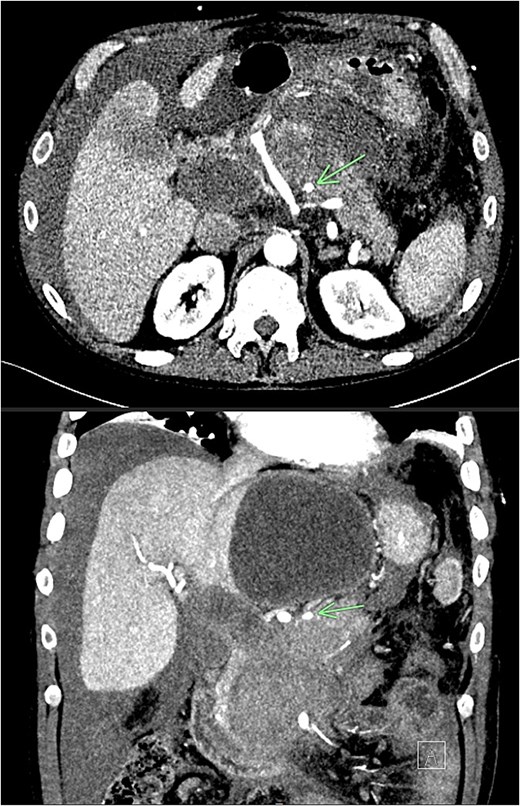

Recovery was complicated by progressive necrotising pancreatitis with evidence of active bleeding into a peripancreatic collection (Fig. 7) and a pseudoaneurysm arising from a branch of the superior mesenteric artery (SMA) associated with haemoperitoneum (Fig. 8).

CT angiogram of abdomen axial and coronal view; small pseudoaneurysm arises from a branch of the SMA (arrow). Large haematoma in the head of the pancreas and diffuse haemoperitoneum throughout the abdomen/pelvis.